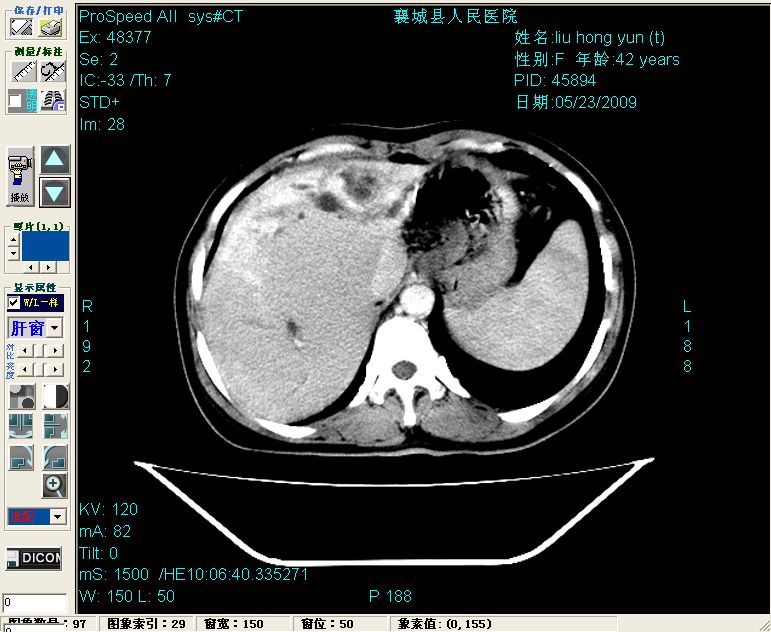

平扫:

平扫左肝外叶体积显著减小,左肝外叶见多房囊性低密度区,左肝实质及右肝前叶浅表实质呈低密度改变,左肝及右肝前叶胆管扩张,脾大